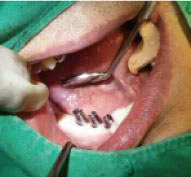

DIO NAVI surgery is planned after 3D computer simulation surgery is done, and it is up-to-date digital navigation implant surgery done with minimal incision and little pain in short time.